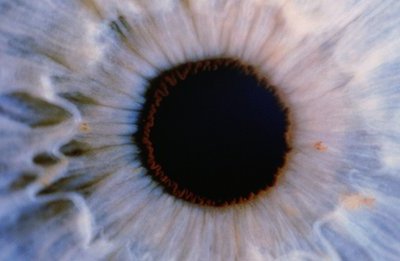

Patients with retinitis pigmentosa gradually lose light-sensing cells from the retina and can become blind.

The research team, at the University of Oxford, used mice with a complete lack of light-sensing photoreceptor cells in their retinas. The mice were unable to tell the difference between light and dark.

They injected “precursor” cells which will develop into the building blocks of a retina once inside the eye. Two weeks after the injections a retina had formed, according to the findings presented in the Proceedings of the National Academy of Sciences journal.